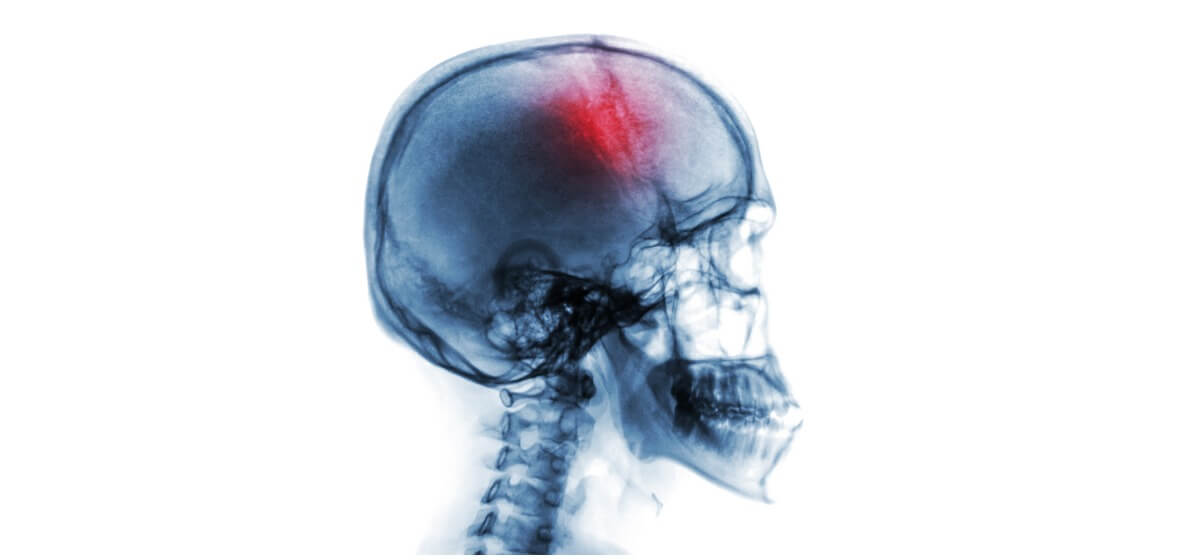

As a young adult, Maddie lived a happy, healthy active life. Then, one day in the shower, she felt the left side of her body go numb and she lost vision in her left eye. Her family rushed her to Baptist East in Louisville where Maddie learned she’d had a stroke. After receiving tissue plasminogen activator (tPA) to minimize the effects of the stroke, Maddie continued undergoing tests which revealed the hole in her heart.